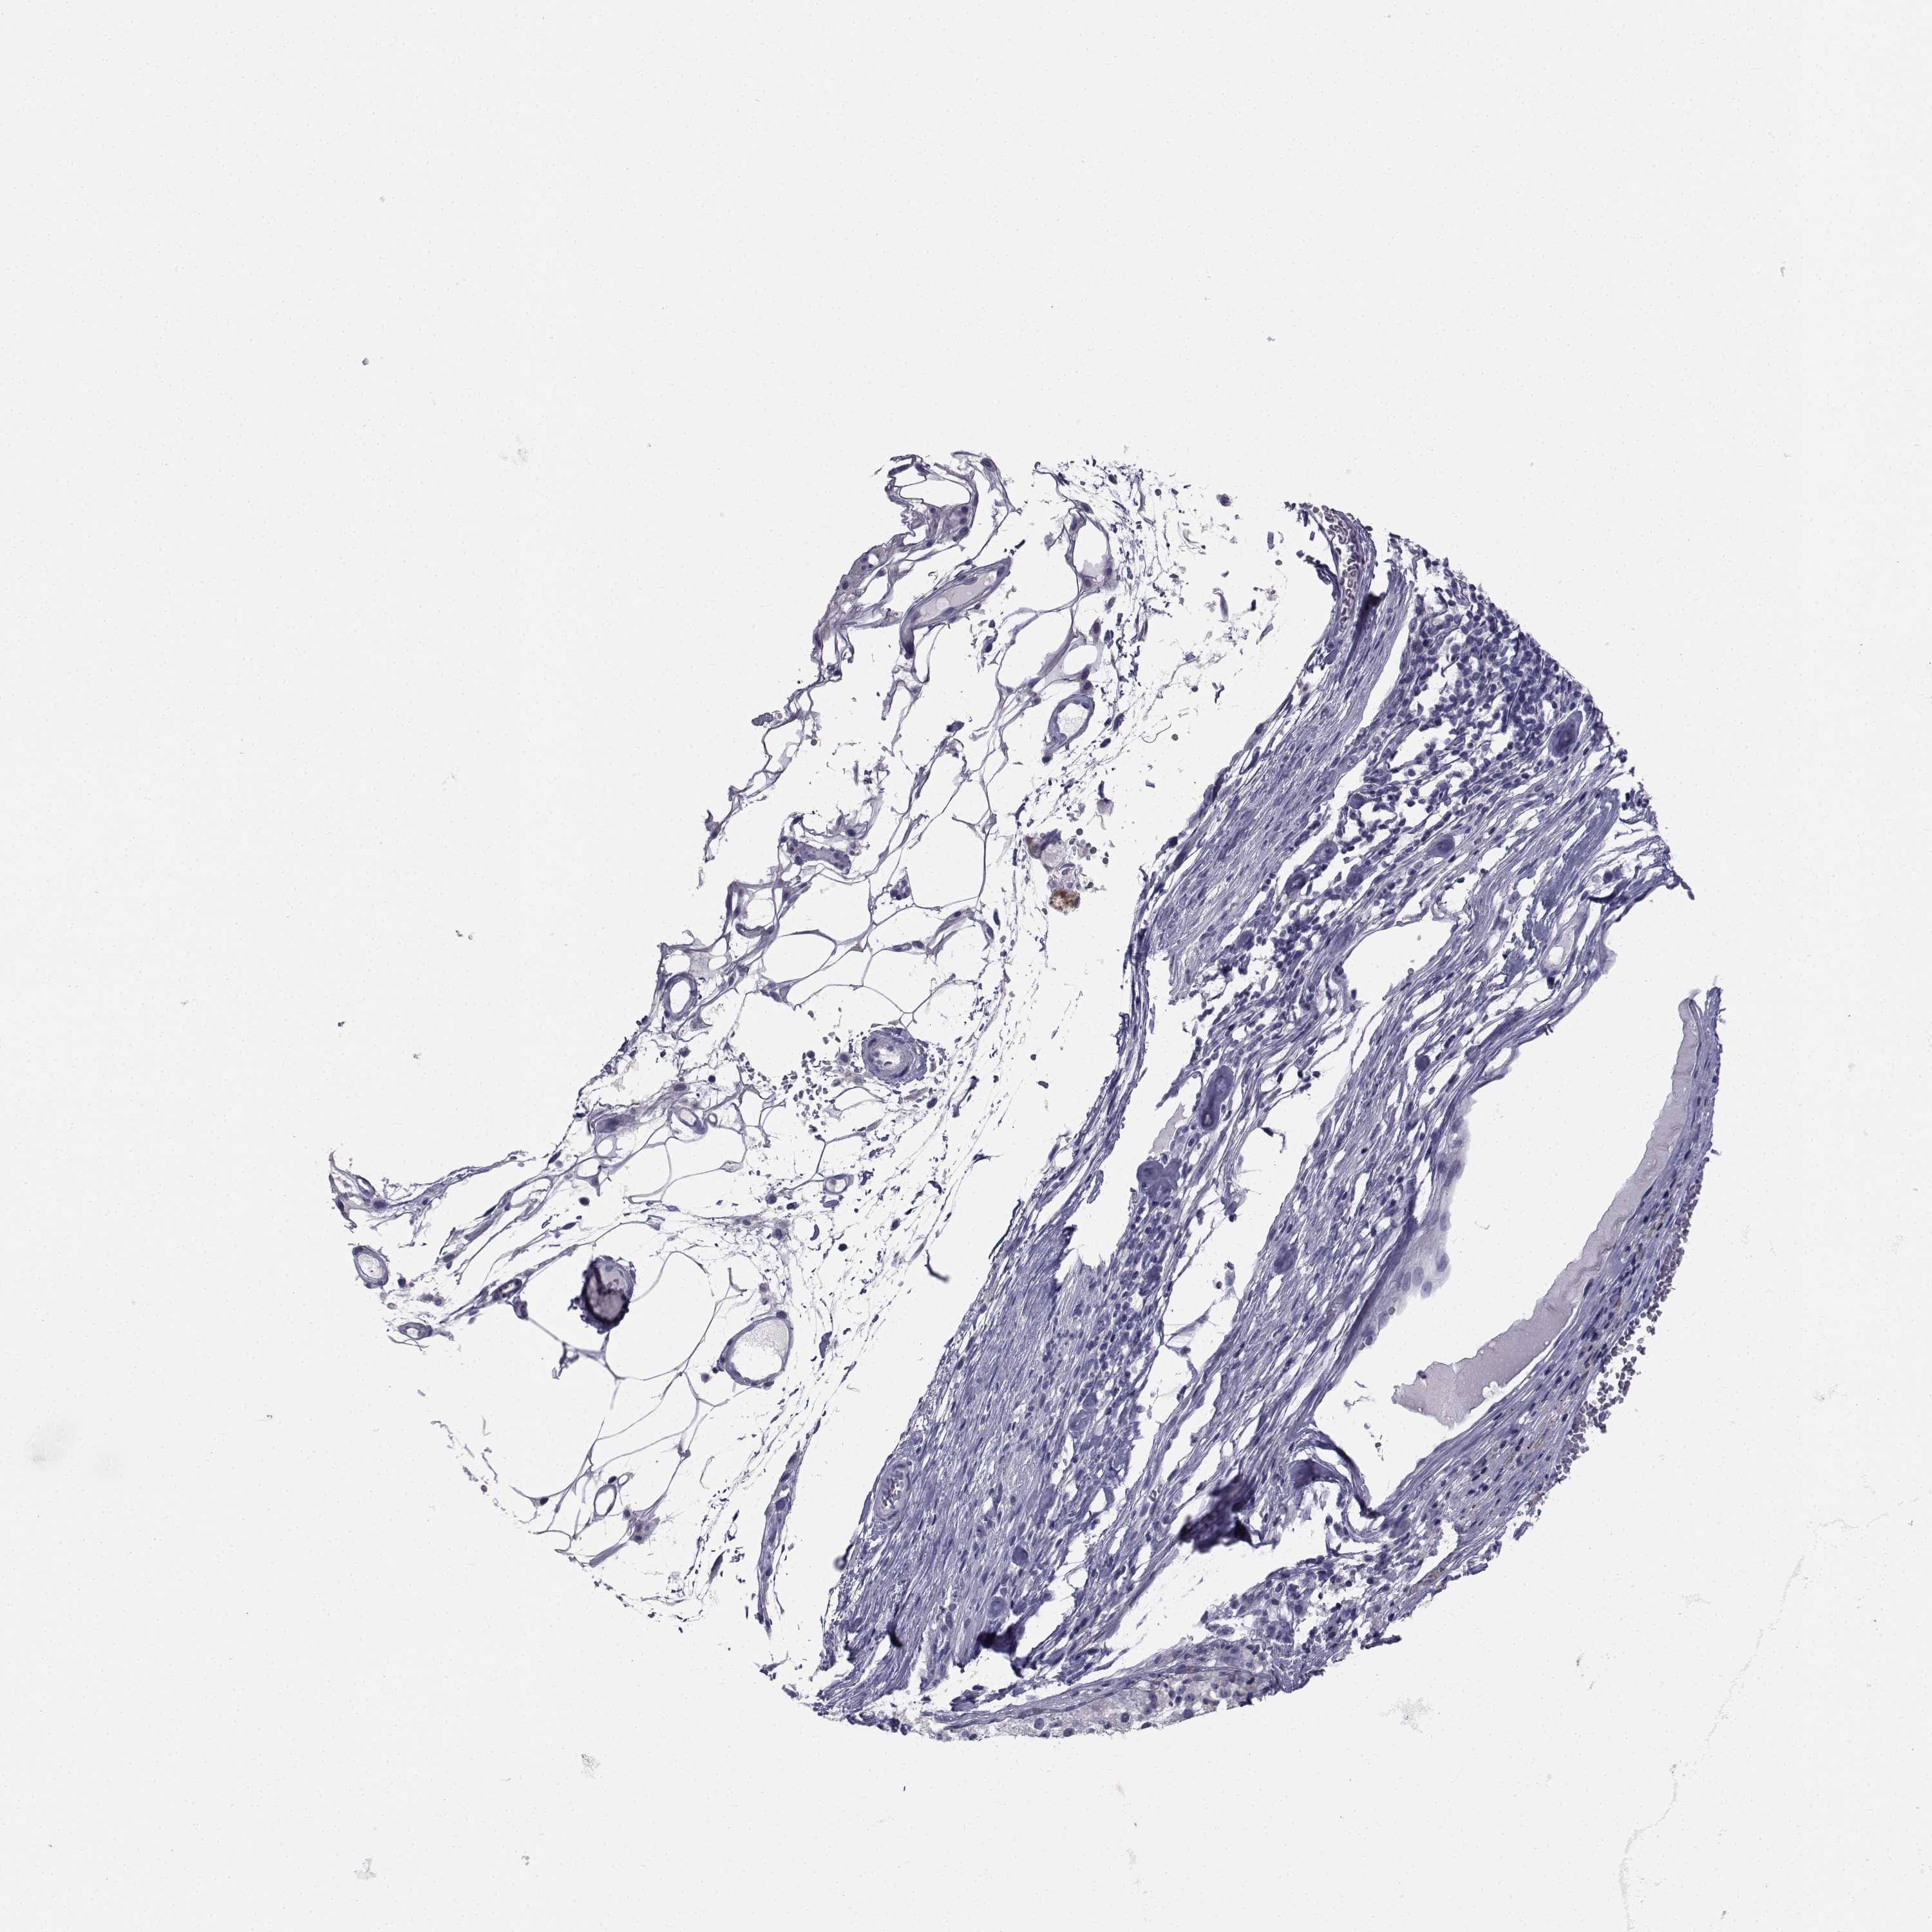

MELANOMA - Protein expressioni

A mouse-over function shows sample information and annotation data. Click on an image to view it in a full screen mode. Samples can be filtered based on level of antibody staining by selecting one or several of the following categories: high, medium, low and not detected. The assay and annotation is described here.

Note that samples used for immunohistochemistry by the Human Protein Atlas do not correspond to samples in the TCGA dataset.

Antibody stainingi

Antibody staining in the annotated cell types in the current human tissue is reported as not detected, low, medium, or high, based on conventional immunohistochemistry profiling in selected tissues. This score is based on the combination of the staining intensity and fraction of stained cells.

Each image is clickable and will lead to virtual microscopy that enables deeper exploration of all samples and also displays staining intensity scores, fraction scores and subcellular localization as well as patient and tissue information for each sample.

Antibody HPA071554

Staining

High

Medium

Low

Not detected

Intensity

Strong

Moderate

Weak

Negative

Quantity

>75%

75%-25%

<25%

None

Location

Nuclear

Cytoplasmic/membranous

Cytoplasmic/membranous,nuclear

Malignant melanoma, NOS

Malignant melanoma, Metastatic site